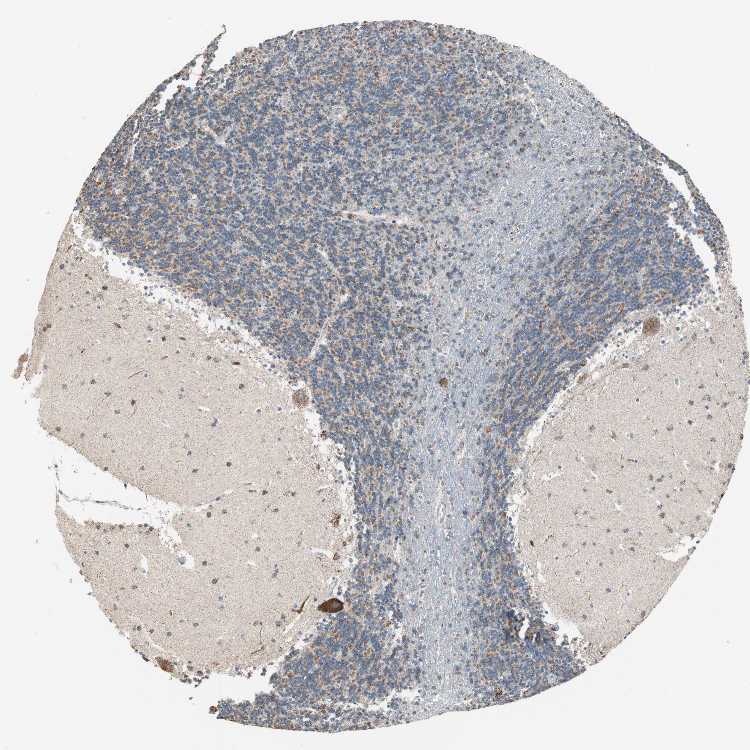

CEREBELLUM - Antibody stainingi

Antibody staining in the annotated cell types in the current human tissue is reported as not detected, low, medium, or high, based on conventional immunohistochemistry profiling in selected tissues. This score is based on the combination of the staining intensity and fraction of stained cells.

Each image is clickable and will lead to virtual microscopy that enables deeper exploration of all samples and also displays staining intensity scores, fraction scores and subcellular localization as well as patient and tissue information for each sample.

Antibody HPA005572

Purkinje cells High

Cells in granular layer Medium

Cells in molecular layer High